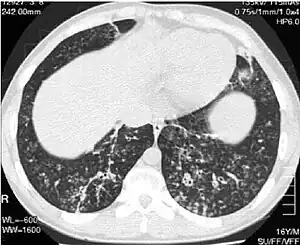

High-resolution computed tomography scan of the thorax -

High resolution computed tomography (HRCT) images of the lower chest in a 16-year-old boy initially diagnosed with DPB (left), and 8 weeks later (right) after a 6-week course of treatment with erythromycin. The bilateral bronchiectasis and prominent centri-lobular nodules with a "tree-in-bud" pattern shows noticeable improvement.